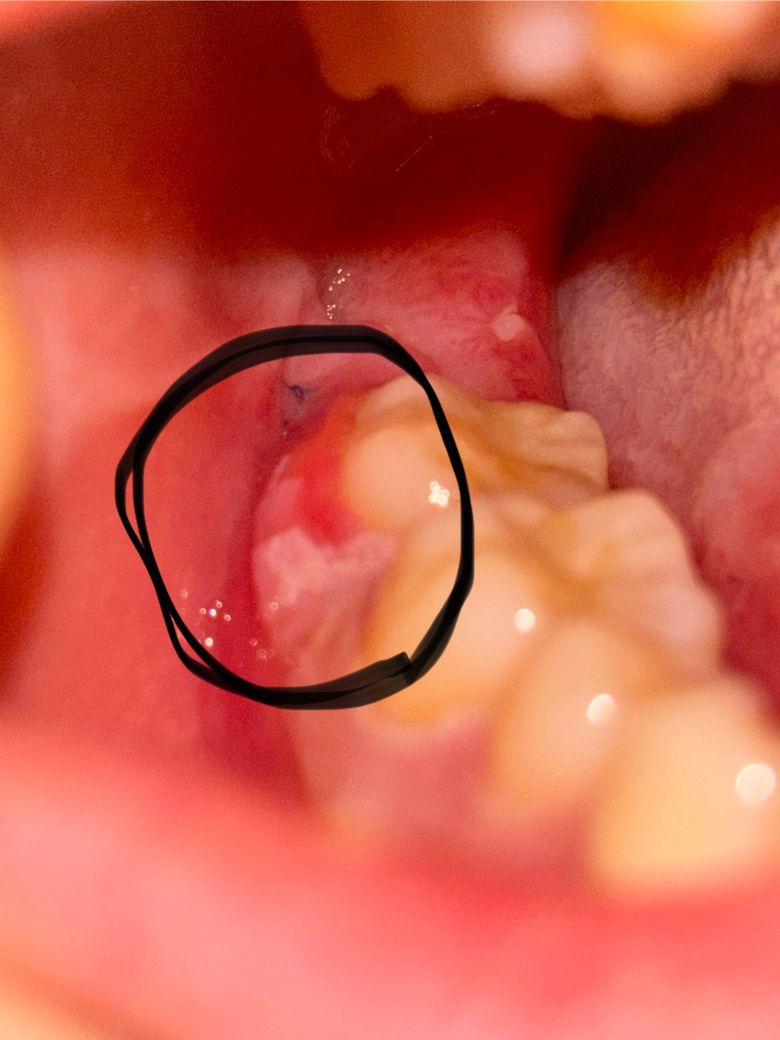

사랑니 발치 후 어금니쪽 잇몸에 염증이 생겼는데 병원 당장 안 가도 되나요?

제목 그대로 사랑니 발치한 후 (오늘 6일차입니다) 발치한 부분 말고 바로 옆 어금니쪽 잇몸(볼살?하고 닿는 부분)이 부으면서 까지듯이 된 게 아직도 아물지를 않아서요... 겉으로 봤을 때 볼이 붓지는 않았어요

그런데 가만히 있으면 통증도 좀 욱신욱신 있고 ㅜㅜ 이빨이 시린 느낌이 들어요

• 1번 째 사진

발치와 연관이 있을지 정확히 판단은 어려우나 사진의 양상으로는 바이러스 또는 세균감염이 의심됩니다 연휴에도 하는 타치과에서 진단받으시고 항바이러스 또는 항세균 연고 처방받으시기 바랍니다